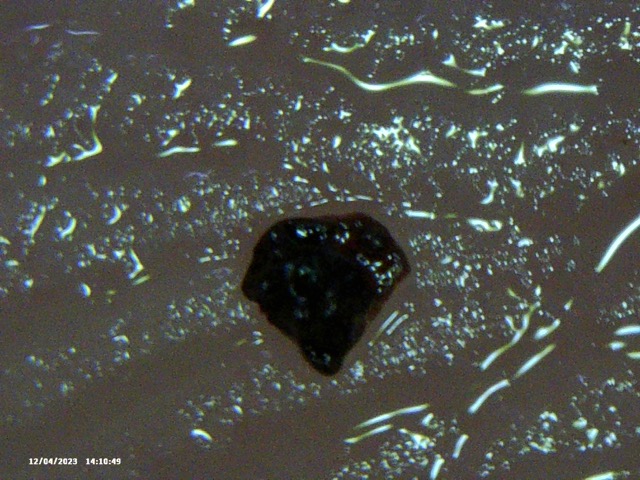

Below is the selection of recent images that I showed him. In isolation they look like they could be ‘anything’ – but with the context of my described condition, and the consistency of objects being extracted, I thought this might, at a minimum be considered ‘not right’ and warrenting further investigation. Silly me.

Image Notes:

- That is my fingerprint in the background.

- All objects are recent and have been extracted over the last 2 weeks

- I simply cannot see some of these objects – however I can feel them, ROCK HARD.

- This is a small selection of what I’m taking out of my skin where I am feeling movement, there are literally 100’s of these things. Imaging them become’s pointless as they are similar.

- Average Distance between fingerprint ridges is 0.15mm for a sense of scale.